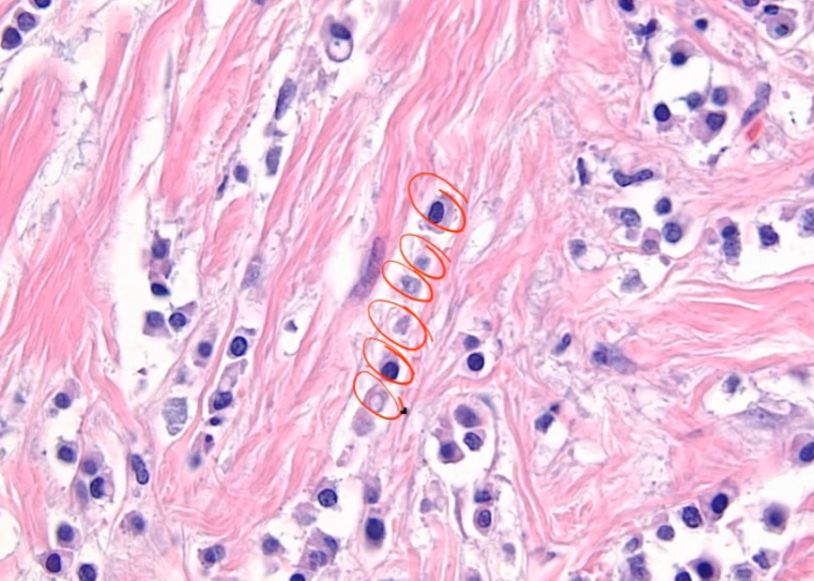

The following image represents the _____ carcinoma subtype of invasive ductal carcinoma (breast): hint: the circled area is lymphatics